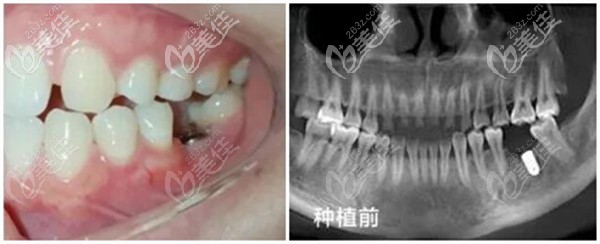

种植前牙齿情况:左边下颌一颗大牙龋坏、缺失;因从小喜欢吃甜食,口腔卫生做的又不到位,导致左下第1磨牙龋坏,(浅龋的时候不重视,一拖再拖一直到蛀牙发展到无法保留),只能拔掉。

CBCT全景片检查,牙槽骨可用骨高度约16.00mm、可用骨宽度约11.80mm,条件良好、无炎症,符合做牙齿种植的需求。